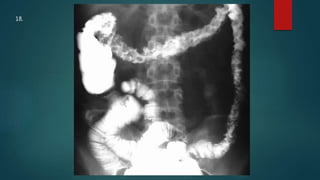

This document appears to be a medical report discussing several patients. It mentions a 35-year-old who was in a severe motor vehicle accident and an 81-year-old with a history of a non-vegetarian diet who had a perforated bowel from a chicken bone. The document provides few other details across its 25 numbered entries and was authored by Dr. Anish Choudhary for junior year 3 on May 30, 2016.